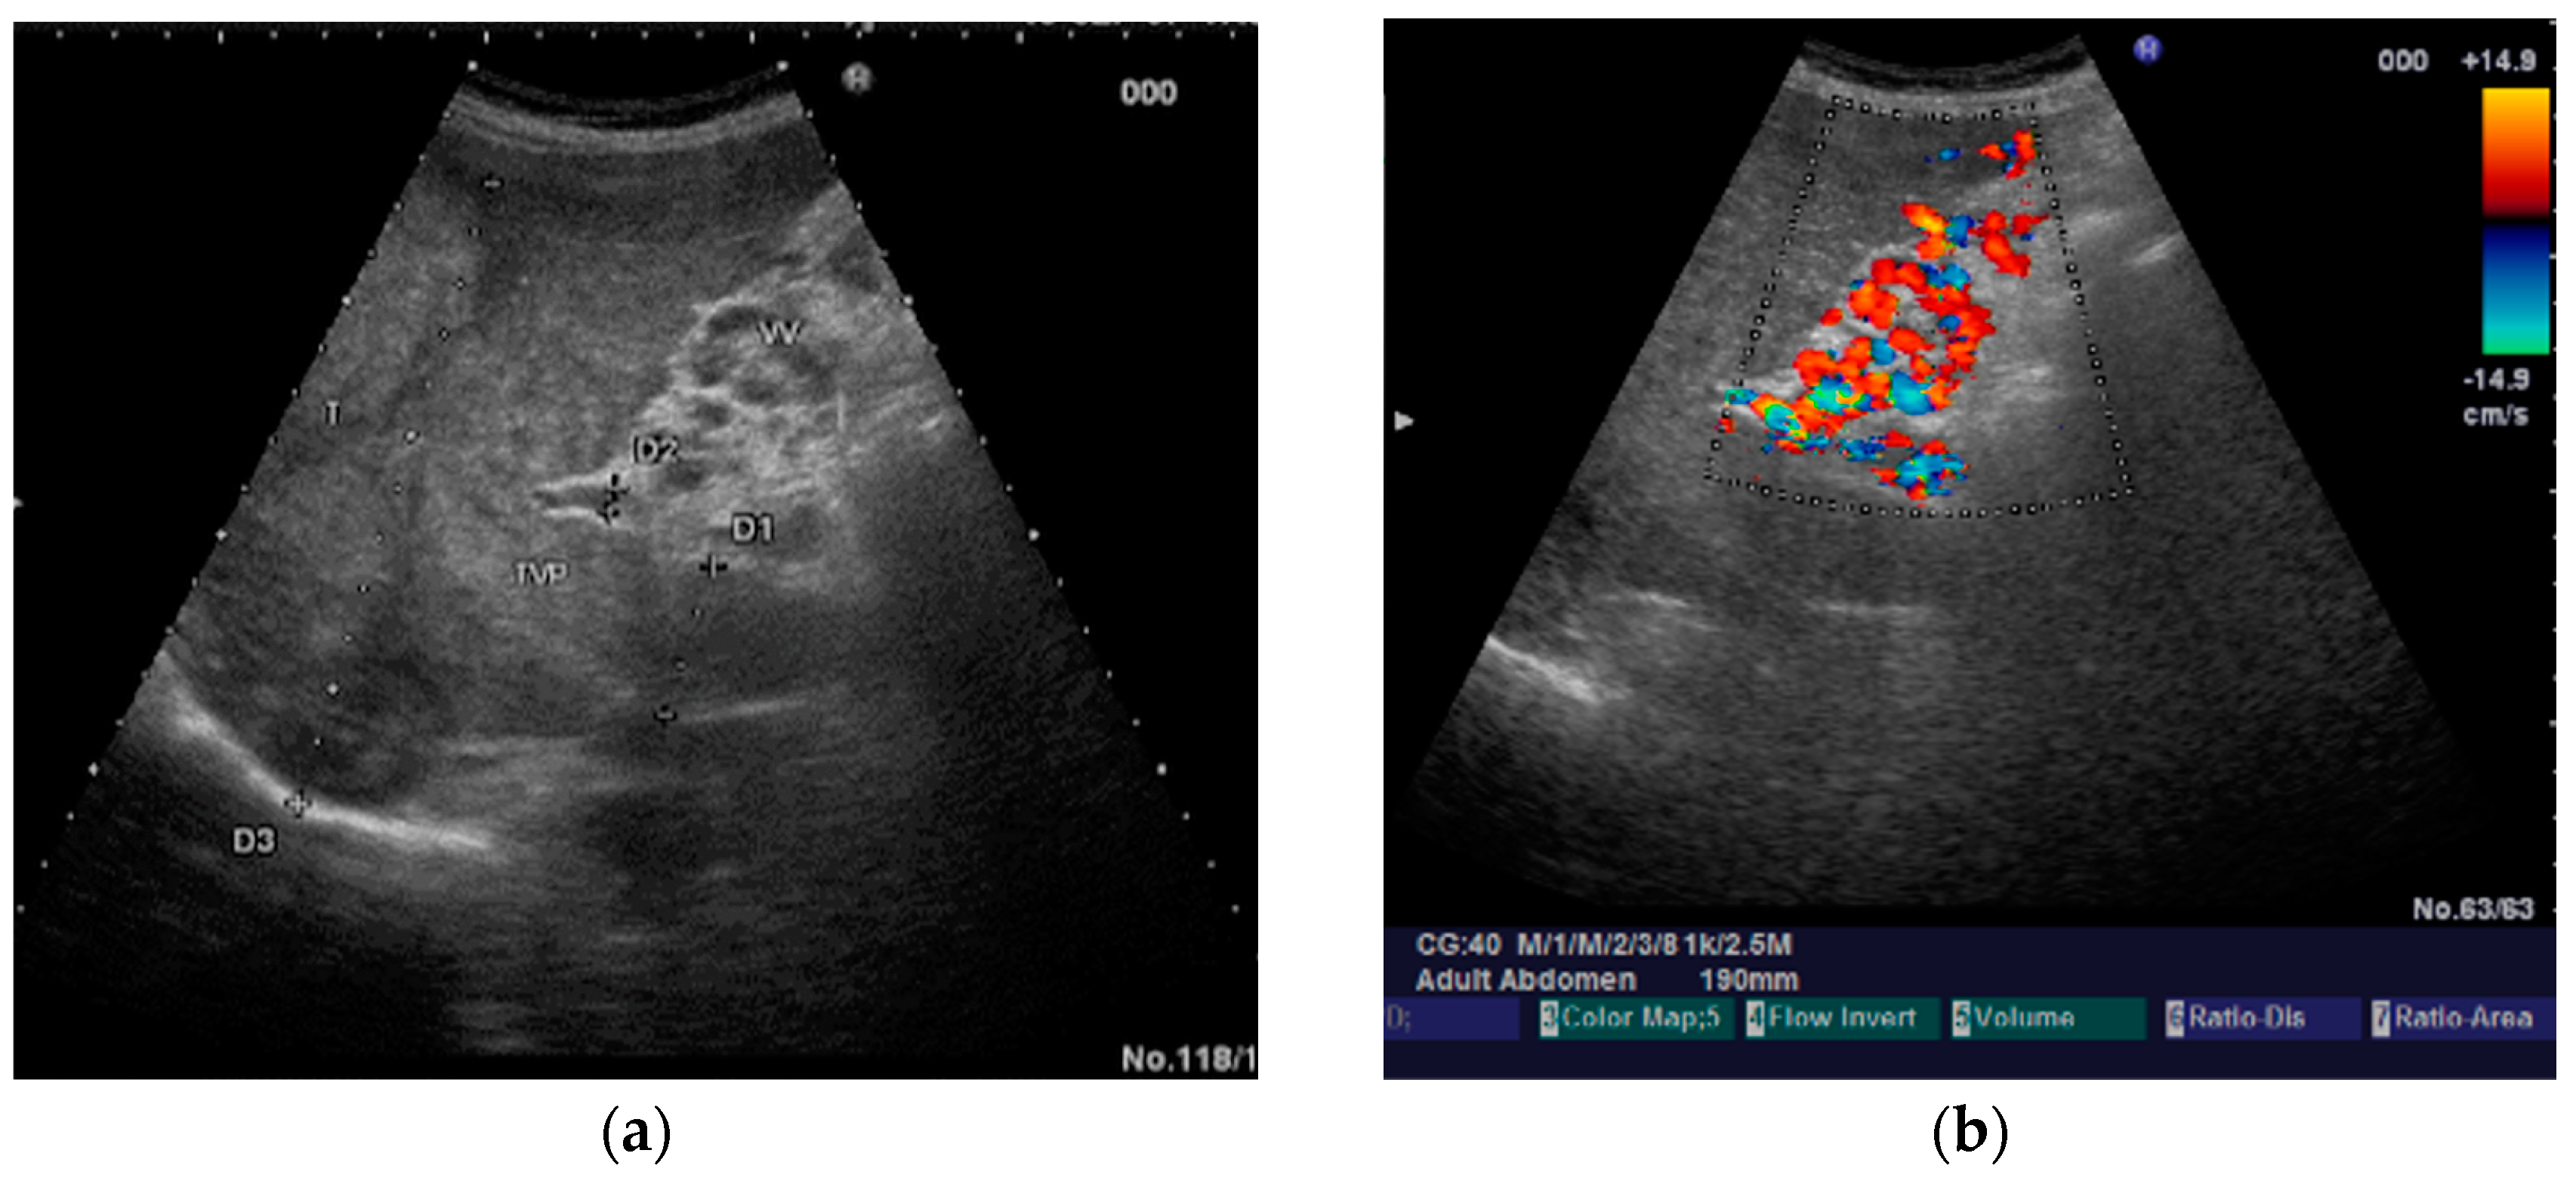

The diagnosis of PVT and PC is made by imaging procedures (transabdominal ultrasound with a Doppler or contrast-enhancing computed tomography scan, magnetic resonance imaging, or angiography in the case of therapeutic intended procedures) [1,3,12,13,14,21,29]. Transabdominal ultrasound is a reliable procedure in 60–100% of cases, with an anechoic aspect in recent cases (requiring Doppler examination or CEUS) and a hypoechoic or hyperechoic aspect in chronic cases [22,29]. Doppler examination may show an anechoic or hypoechoic thrombus and a slower (<15 cm/sec) or absent portal blood flow, and is considered the gold standard (color Doppler) for the diagnosis of PC [1], with a sensitivity and specificity of 95% (Figure 1 and Figure 2) [22]. CEUS can help the diagnosis of benign or malignant PVT, can characterize associated focal liver lesions [30], allows a better characterization of PVT [31], and also permits better detection of PC—Figure 3 and Figure 4 [32]. CT scan and MRI (Figure 5 and Figure 6) are more accurate for the evaluation of liver causes (HCC, abscesses, and other tumors) or other local causes (pancreatitis, diverticulitis, and appendicitis), and for complications (bowel infarction or perforation), and may show permeability of the portal venous system and the flow direction [1,22]. Malignant PVT has intra-thrombus arterial signals on CT, MRI, and/or CEUS, with portal vein diameter frequently 23 mm or above, and with the presence of the tumor at imaging examination (Figure 4 and Figure 6) [21].

Figure 1.

Portal cavernomatous transformation. (a) Multiple serpiginous echo-free structures (vessels) replacing the normal portal vein are seen in B-mode at the hepatic hilum; (b) Color Doppler examination confirms the presence of venous flow within the vessels of the cavernoma.

Transabdominal ultrasound with Doppler protocol (Figure 1a,b and Figure 2a,b), CT scan (Figure 3a,b), and MRI (Figure 4a,b) were used for the diagnosis in 88.9, 75.1, and 15% of cases, respectively. CEUS was used for the diagnosis in 49 cases (25.9%) but in only 29 cases was it used for the evaluation of the thrombus, and in two cases for cavernoma diagnosis (Figure 5a,b and Figure 6a,b).